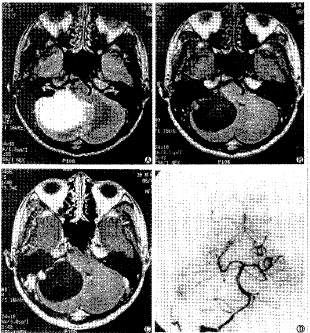

图3 A、B. T2、T1像可见右侧小脑半球囊结节型血管网质细胞瘤 C. T1增强像:可见肿瘤结节增强 D. 可见右侧小脑结节样染色,小脑前下动脉,脑膜血管供血

(1)平扫示:实质型8例,可见肿瘤实质部分呈等T1等T2信号,囊腔无或很小,肿瘤囊腔呈长T1长T2信号。边缘欠清,7例可见边缘血管流空影,6例可见肿瘤周围有稍长T1长T2的水肿,只有1例可见肿瘤内有短T1长T2的出血。最大肿瘤55mm×50mm×35mm,最小3mm×3mm×5mm。囊实质型11例,肿瘤实质内或外可见单个或多个稍长T1长T2的囊腔,9例可见边缘血管流空影,8例肿瘤周围有长T1长T2水肿,最大肿瘤50mm×55mm×45mm,最小15mm×10mm×8mm。囊结节型8例,可见大的单个的长T1长T2信号的囊腔,边缘清,周围无水肿,肿瘤多较大,无边缘血管流空影。最大肿瘤68mm×55mm×50mm,最小10mm×10mm×20mm。21例可见压迫四脑室、中脑导水管,引起梗阻型脑积水。10例可见小脑扁桃体下疝。

(2)增强示:22例行增强扫描。实质型6例,囊实质型10例,囊结节型6例。增强可见肿瘤实质部分均匀强化。囊结节型可见囊壁结节增强,囊壁不增强,最小结节3mm×5mm×5mm。见图3。2例为多发病变,1例为右侧囊实质型伴左侧小的实质型小脑半球血管网织细胞瘤。见图4。1例为右侧囊实质型小脑半球肿瘤伴右颞小的实质型肿瘤。